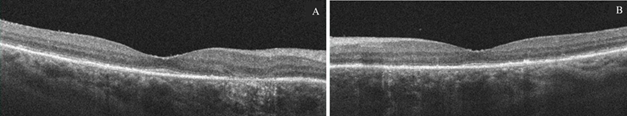

At post-operative week 6 OD and week 4 OS, the patient complained of blurry vision OS > OD with onset 5 days before this visit. Distance visual acuity without correction was 20/400 PHNI OD; HM PHNI OS. Potential acuity meter (PAM) was 20/400 OD, OS. Anterior segment examination revealed toric intraocular lens implants in good position but partially obscured by the white fibrotic anterior capsule remnant in both eyes (Figure 1A, 1B). Examination of posterior segment showed pigmentary changes in the macula of both eyes that were unchanged from the pre-operative evaluation. Optical coherence topography (OCT) macula of both eyes showed no changes when compared to scans taken at the pre-operative evaluation. The patient was diagnosed with bilateral anterior capsular phimosis and scheduled for Nd:YAG laser capsulotomy in both eyes.

The patient underwent uneventful Nd:YAG laser capsulotomy in the left eye, then in the right eye 1 week after that. At Nd:YAG laser capsulotomy post-operative day 4 OD and week 2 OS, distance visual acuity without correction was 20/40 PHNI OD, OS with best corrected visual acuity 20/30 OD, OS (Table 1). Anterior segment examination showed toric intraocular lens implants were in good position with open anterior capsules and closed posterior capsules in both eyes with no significant posterior capsular opacity (Figure 1C, 1D). Posterior segment examination showed pigmentary changes in the macular of both eyes that were unchanged from the pre- operative evaluation (Figure 2A, 2B).

Figure 1 Anterior capsular phimosis in the right eye (A) and left eye (B) at follow-up visit status post cataract extraction with toric intraocular lens implantation week 6 OD and week 4 OS. Open anterior capsule in the right eye (C) and in the left eye (D) at follow-up visit status post Nd:YAG laser capsulotomy at week 3 OD and week 4 OS.

Figure 2 (A) OCT macula of right eye at week 3 status post Nd:YAG laser capsulotomy show RPE changes. (B) OCT macula of left eye at week 4 status post Nd:YAG laser capsulotomy show RPE changes and drusen.